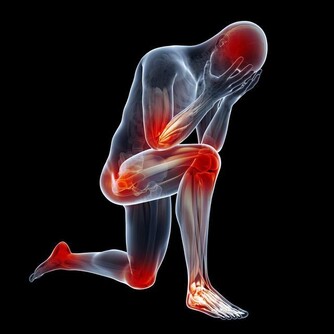

事實上,五十肩的英文名詞是:「冰凍肩」(frozen shoulders),

它的正確名稱是:「粘連性肩關節囊炎(adhesive capsulitis)」簡單說來,

就是關節囊重複累積各種酸痛、發炎後,最後被僵硬的軟組織夾擊,導致關節無法活動。

雖然這種症狀好發於40-60歲之間的族群,但年齡只是參考,

越來越多人年輕人發現手臂「忽然不舉」,才知道竟然是五十肩發作。

造成五十肩的成因很多,因此當肩痛與關節僵硬的情況出現時,

務必就醫接受物理治療,如冰敷,熱敷、超音波、經皮神經電刺激、冷雷射等。

一般民眾如果經常姿勢不良,或慣性使用手臂某些肌肉,也很可能導致潛在的五十肩風險。

一般說來,五十間的僵硬症狀會慢慢自癒,但很容易造成生活不便。